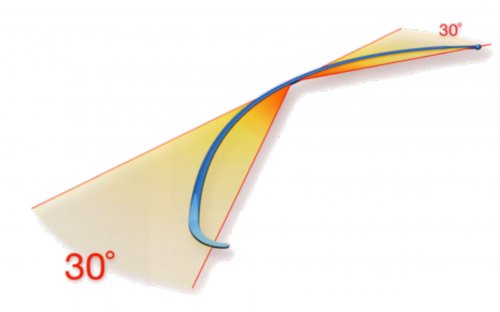

I chiodi vengono pre piegati prima dell’ introduzione con un angolazione di circa 30° (Fig 5) onde determinare il blocco elastico della frattura e i 2 chiodi contrapposti restituiscono le forze in modo dinamico mantenendo la riduzione della frattura e mantenendo il sistema in equilibrio (Fig 6)

Fig 5